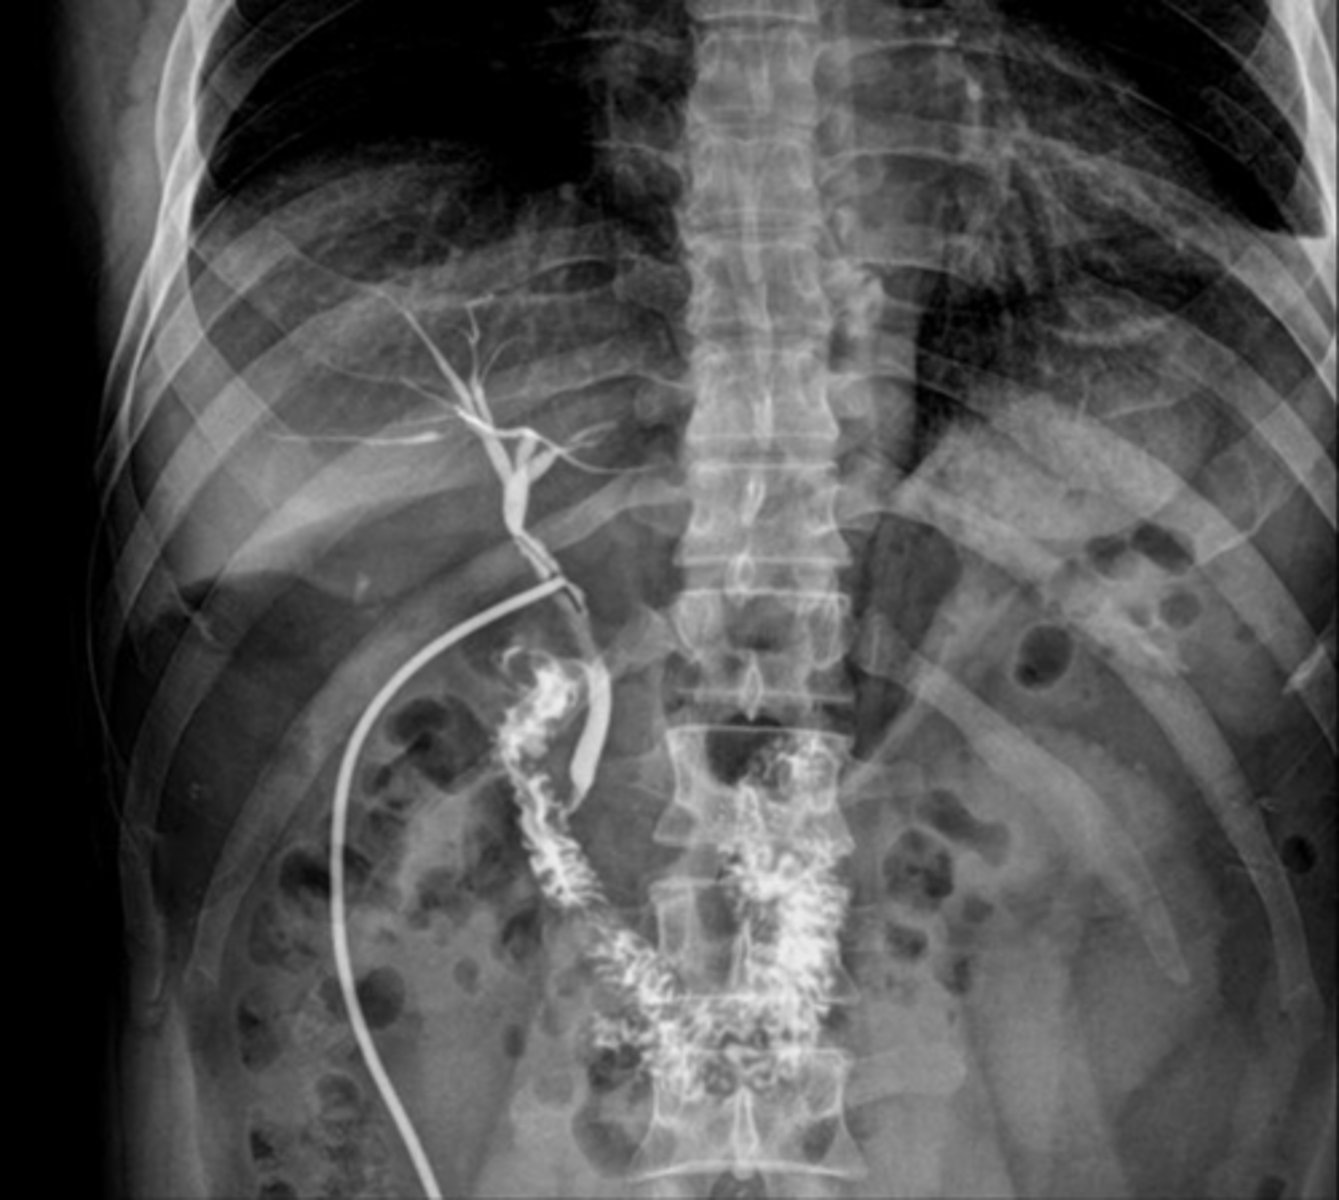

radiographic visualization of bile ducts using XR and contrast, evaluates presence of obstruction or damage of bile ducts

cholangiogram

3 different types of cholangiograms

- intraoperative cholangiogram

- postoperative cholangiogram

- percutaneous transhepatic cholangiography